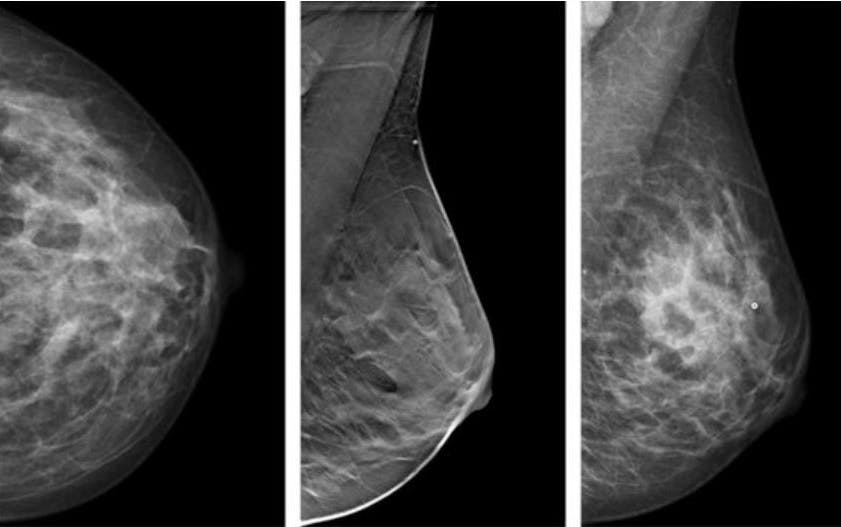

Dies kann die sogenannte Tomosynthese einer schwedischen Studie zufolge anscheinend eher als die derzeit gängige Mammografie, wie ein Team um die Radiologin Kristin Johnson von der Universität Lund im Fachblatt „Radiology“ berichtet. Ebenso wie die Mammografie beruht die Tomosynthese auf Röntgenstrahlen. Aber während die Mammografie gewöhnlich nur zwei Ebenen zeigt, durchleuchtet bei der Tomosynthese eine sich drehende Röntgenquelle die Brust aus verschiedenen Winkeln. Die Bilder werden dann am Computer in ein dreidimensionales Modell umgerechnet – daher wird das Verfahren zuweilen auch 3D-Mammografie genannt.